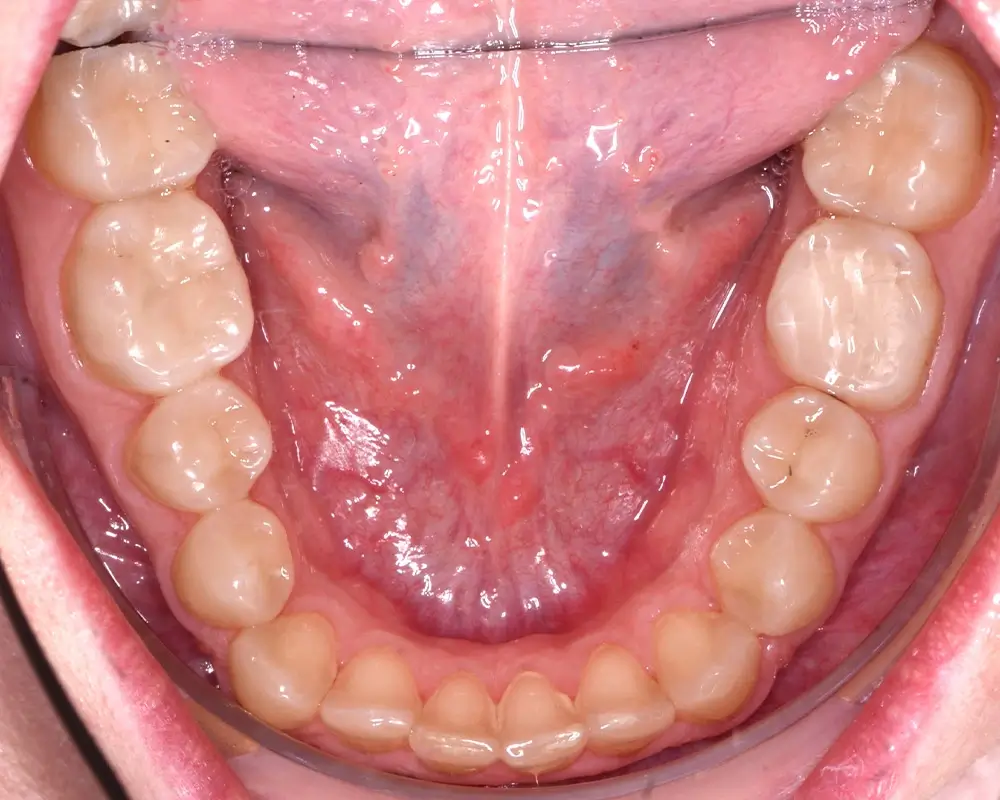

Кейс 8

Бажанова Ольга Валерьевна

Количество кап ВЧ 24

Количество кап НЧ 24

ДО